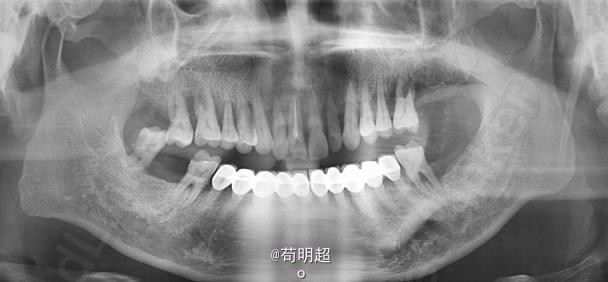

47牙齿种植修复

患者,男,40岁,47牙缺失要求种植。平素体质一般,无药物、食物过敏史,无高血压、心脏病等系统病史。